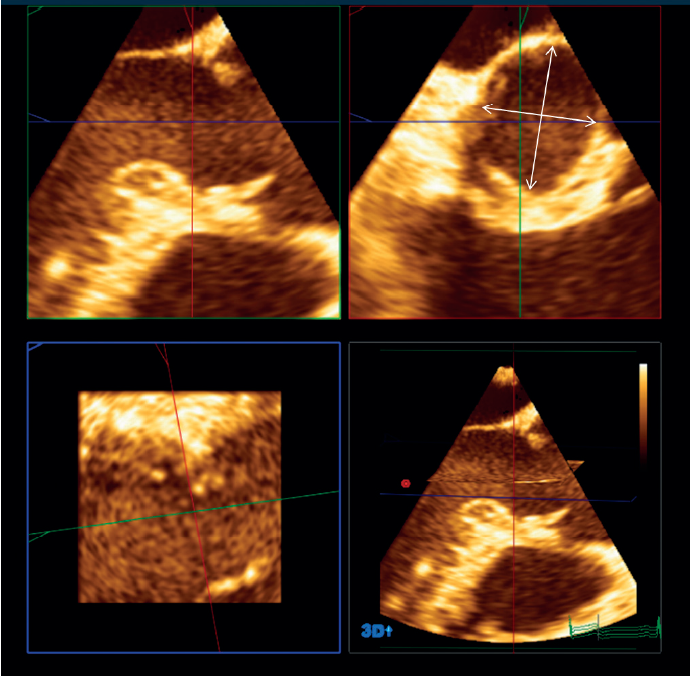

Why The New Severe Aortic Insufficiency After Mitral And ...

LEAFLET BY MITRAL ANNULOPLASTY SUTURES The midesophageal aortic valve long-axis color Doppler window demonstrated new, image after mitral and tricuspid valve repair showing new, eccen-trically directed, severe aortic insufficiency. Fig 6. ... Fetch Content